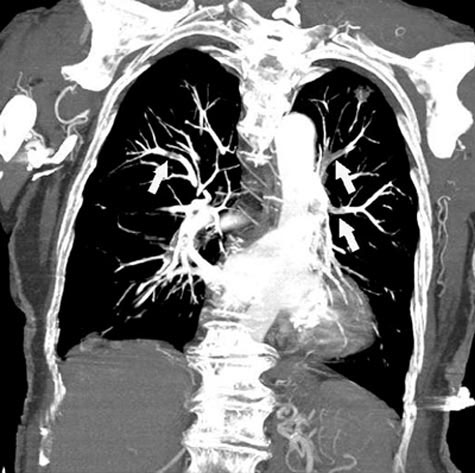

Embolia pulmonar (angiografia por TC)

Angiografia por TC mostrando múltiplos êmbolos bilaterais.

Com a permissão do editor. De Kucher N, Goldhaber S, Sewell J, et ai. In Bone's Atlas of Pulmonary and Critical Care Medicine. Editado por J Crapo. Philadelphia, Current Medicine, 2005.